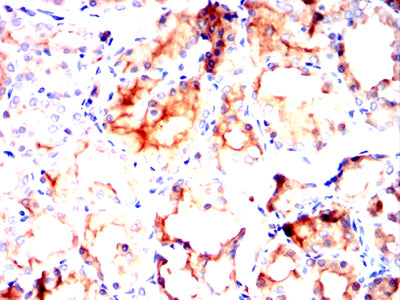

![MUC13 Mouse mAb[63965]](https://img1.dxycdn.com/p/s14/2025/0922/850/0274370026746699691.jpg)

Immunohistochemical analysis of paraffin-embedded Rat thyroid tissues using MUC13 mouse mAb with DAB staining.